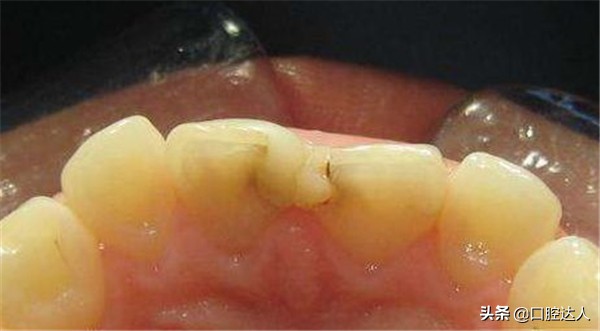

剩下的一部分就没那么幸运了,出现这种疼痛表明牙髓组织已经不再健康,需要做根管治疗。补完牙后慢性牙髓炎发作,慢性牙髓炎发作没有什么明显的症状,所以说很多患者并不觉得疼。补牙之后,会出现隐隐的自发痛,实际上这颗牙齿在补牙之前就已经有了慢性的牙髓炎,那就还逃不过根管治疗这一步。

如果是釉质和填充物之间的粘接剂发生了分裂,食物残渣和致龋因子会进入缝隙,引起继发龋。